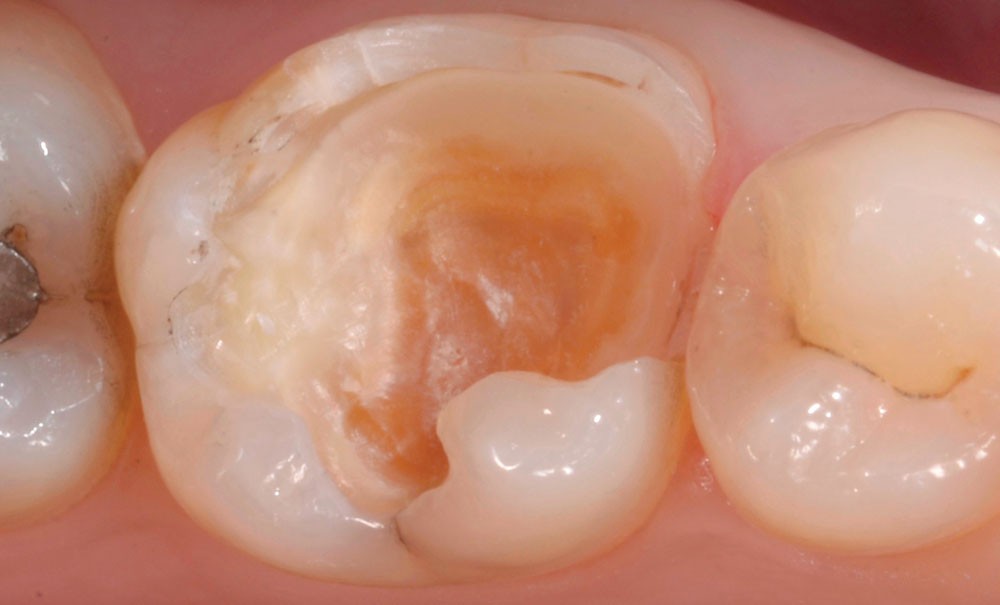

Les parois résiduelles dans les cavités à inlay/onlay de plus de 2 mm d’épaisseur peuvent généralement être conservées sans risque de fracture. Celles de moins de 1 mm d’épaisseur doivent en revanche être abaissées et recouvertes car leur risque de fissuration lors de la mastication est trop important. Les parois d’épaisseur intermédiaire (1 à 2 mm) seront recouvertes préférentiellement :

- lorsqu’il s’agit d’une molaire ;

- lorsqu’il s‘agit d’une cuspide guide ;

- en présence de parafonction ;

- lorsqu’il n’y a plus de crêtes marginales ou de pont d’émail ;

- lorsque la cavité est très profonde ;

- lorsque la dent est dépulpée ;

- en présence d’émail non soutenu par de la dentine ;

- en cas de dyschromie persistante.